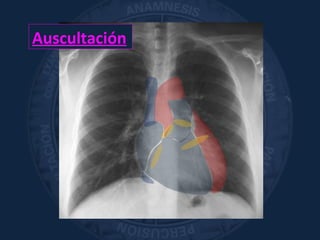

Auscultación

«apreciación con el sentido del

oído de los fenómenos acústicos

que se originan en el organismo»

Laënne

Sist. Circulatorio

Sonidos cardíacos normales, soplos, sonidos agregados.

CARÓTIDAS. Art. RENALES

Pulmón y Vía Aérea

Ventilación alveolar, alteraciones en el flujo aéreo,

sonidos agregados

Abdomen

Ruidos hidroaéreos/Borborigmos